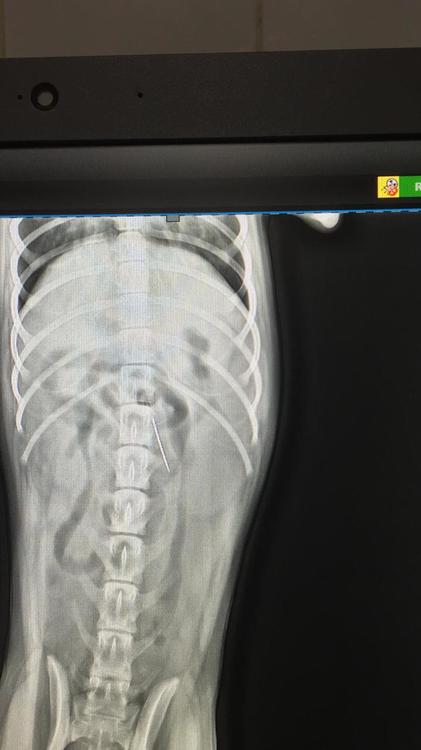

taf82 Опубликовано 9 июня, 2019 Опубликовано 9 июня, 2019 29 минут назад, Дони сказал: завтра кину немного. карту найду в теме? Лена а что случилось то? Стырила и размотала катушку с нитками, а в ней была иголка. Как выяснилось иголку она проглотила и та встала в кишечнике...

taf82 Опубликовано 9 июня, 2019 Опубликовано 9 июня, 2019 29 минут назад, Ольга и Огонёк сказал: Ужас. Вот мелкая засранка чего же теперь, оперировать? Уже